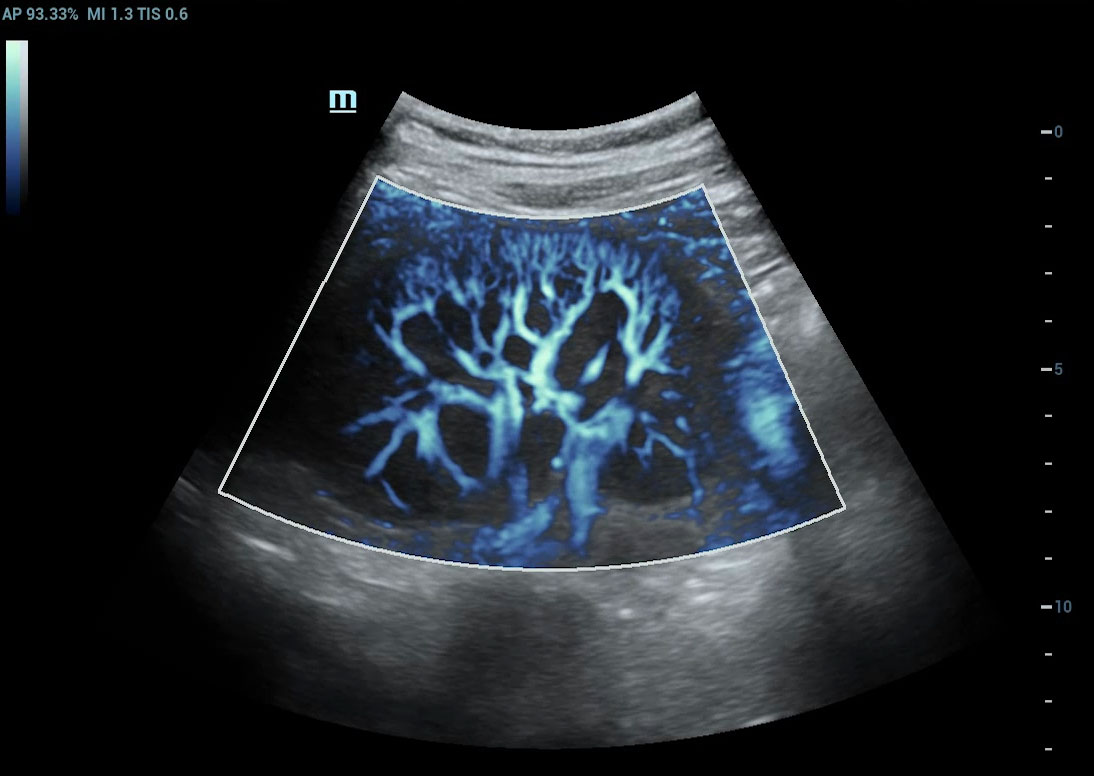

Ultra-Micro-angiografie (UMA)

UMA verbetert het diagnostische vertrouwen door de zichtbaarheid van de bloedstromen uit te breiden tot op het kleinste vaatniveau, met een superieure gevoeligheid en resolutie van de bloedstroom.

sUMA Nier

sUMA Schildklierkanker

Beeldengalerij

Lymfeklieren sUMA

Varicocele beglazing sUMA